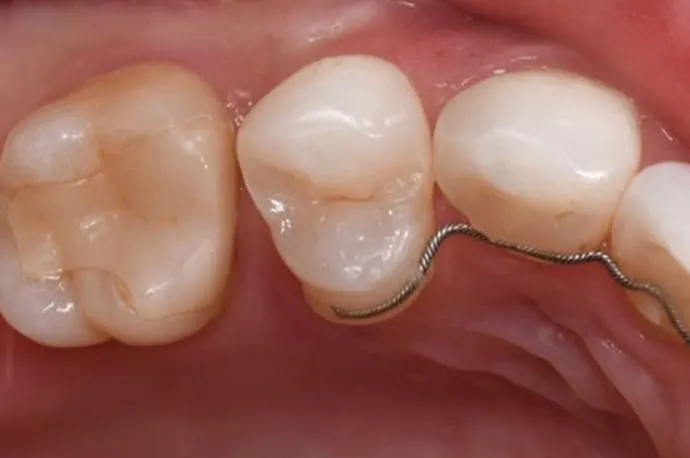

歯周病の検査

歯ぐきや歯の周りの状態をチェックします。

歯石の除去

歯の表面や歯ぐきの下の歯石を取り除き、炎症を防ぎます。

PMTC(プロフェッショナルケア)

回転ブラシなどを使い、歯の汚れや着色をしっかり落とします。

歯磨き指導

患者さま一人ひとりに合ったブラッシング方法をアドバイスします。